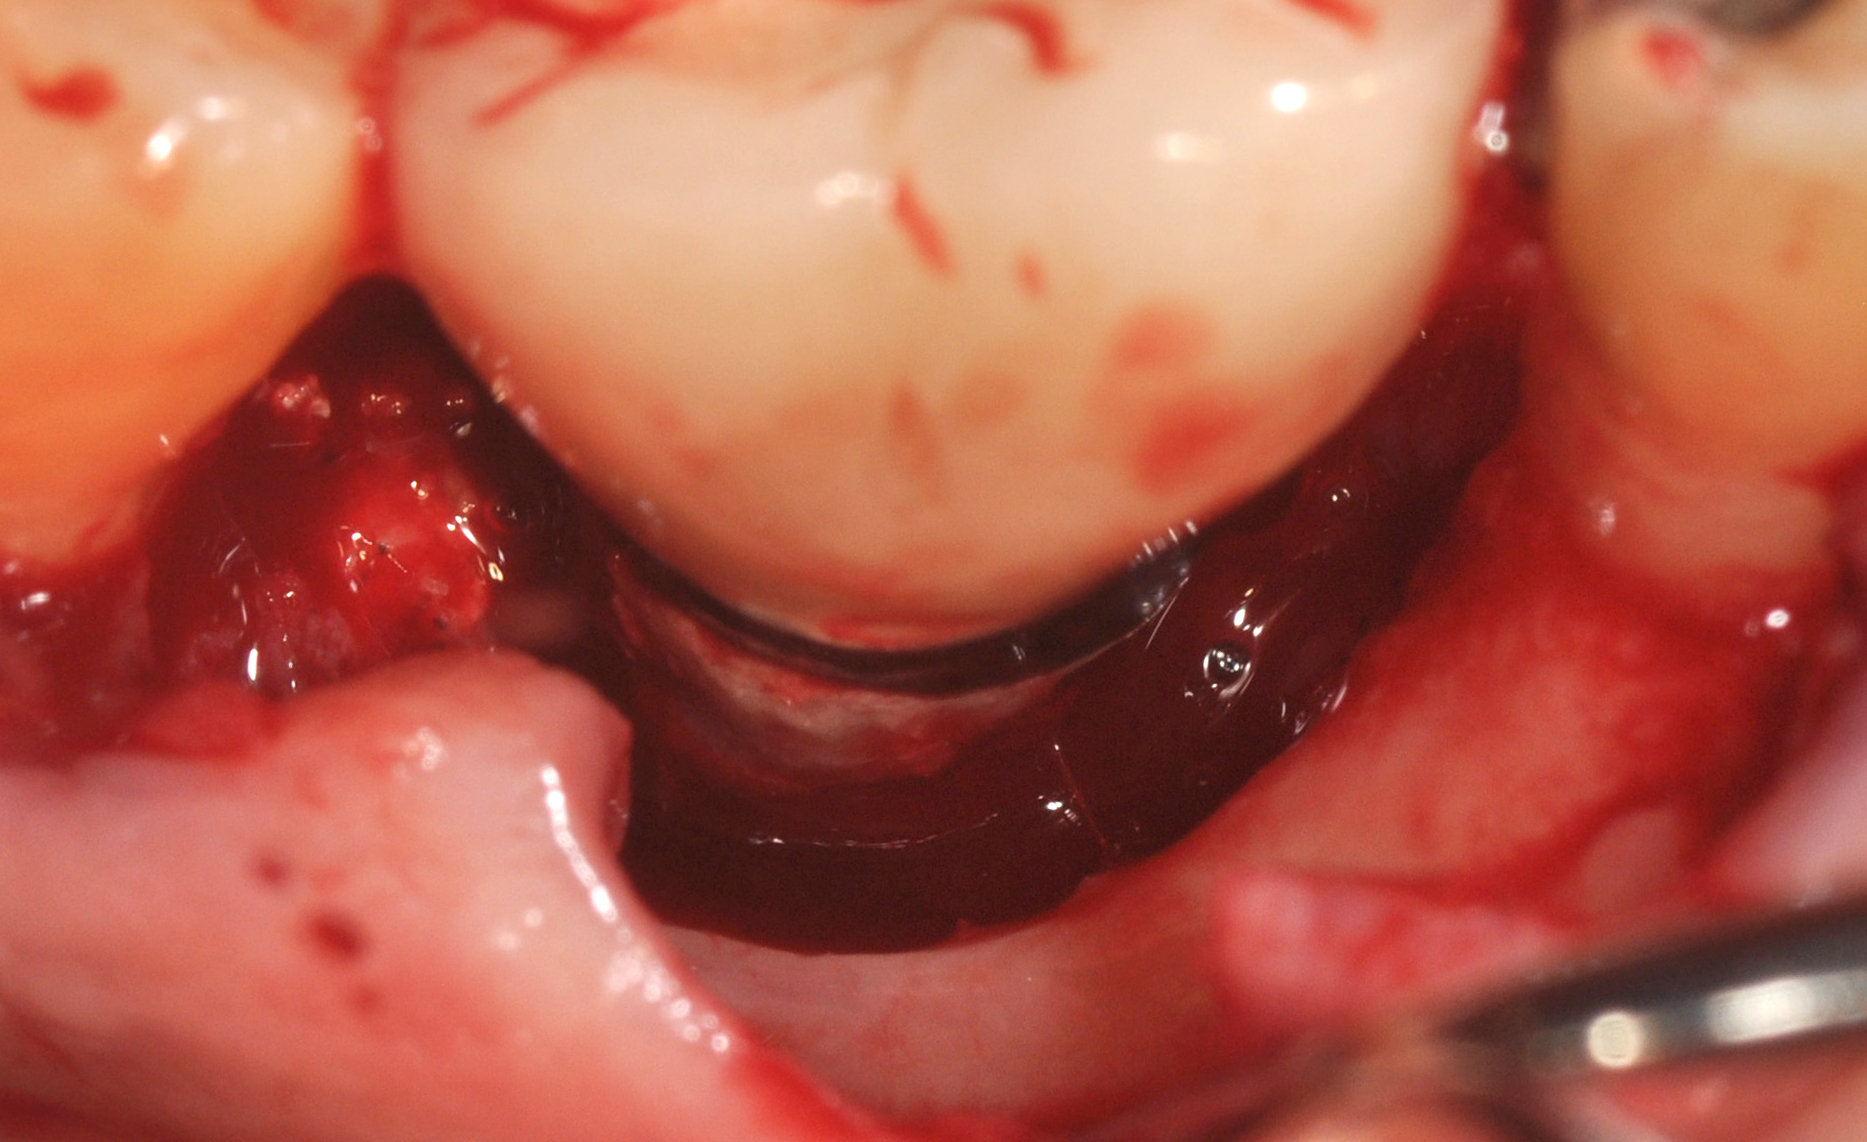

Clinical examination showed 2 mm of buccal recession with a shallow vestibule and absence of keratinized attached gingiva against the crown with 8 mm of circumferential pocketing accompanied by bleeding upon probing (Figure 15 and Figure 16). A periapical radiograph showed a symmetrical vertical osseous defect causing the loss of 50% of the bone around the implant (Figure 17). Because the patient had made a significant investment of time and finances to replace her lost tooth with the implant, she desired that the implant and restoration be retained, if feasible.

A surgical flap procedure was performed with the intent of thoroughly debriding the granulomatous tissue from the osseous defect (Figure 18 and Figure 19), mechanically and chemically detoxifying the surface of the implant (Figure 20 through Figure 22), and grafting the infrabony component of lesion with bone xenograft (Bio-Oss®, Geistlich Pharma, www.geistlich-na.com) in an attempt to reduce the vertical defect (Figure 23). To concurrently resolve the mucogingival problem, the plan called for placing a dermal allograft (Dermis Allograft, DENTSPLY International, www.dentsply.com) on the buccal (Figure 24) and then replacing the flap (Figure 25).

Fig 18. A full-thickness flap from teeth Nos. 18 to 20 revealed granulomatous tissue in the circumferential defect around implant No. 19.

Figure 18

Fig 19. The circumferential defect was debrided. Note excess cement extending apically from the margin of the crown into the defect; residual cement has been shown to be complicit in the development of peri-implant disease.